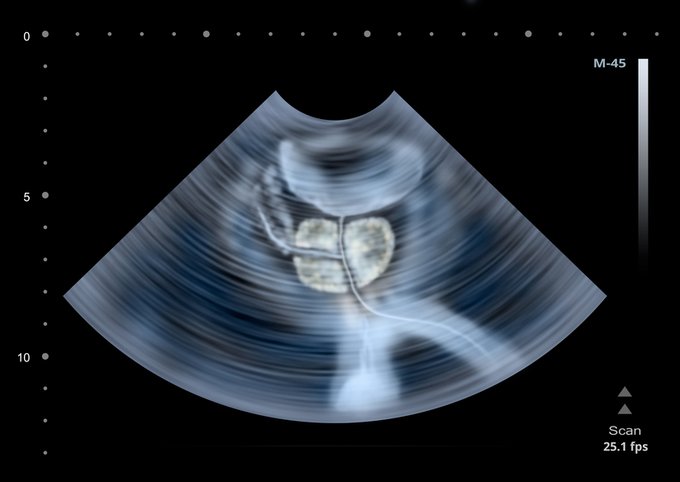

¿Sabías que el cáncer de próstata es común en hombres mayores, pero es raro en menores de 40 años? ¿Cuáles son sus factores de riesgo? Entérate aquí ow.ly/NCcx50AVd7N